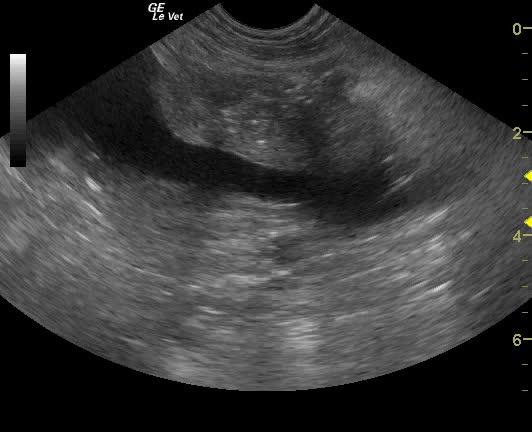

A 9-year-old intact female Brittany Spaniel dog, with previous history of cystotomy, was presented on emergency at a 24-hour facility for vomiting, shaking, painful abdomen, and extreme lethargy. Physical examination found the patient whining and crying, depressed, with tacky mucous membranes, and a firm distended abdomen. The patient was ambulatory but was most comfortable in sternal recumbency. Abnormalities on CBC and blood chemistry included leukocytosis, increased BUN, and mild hypoalbuminemia. Coagulation panel was within normal range.

A 9-year-old intact female Brittany Spaniel dog, with previous history of cystotomy, was presented on emergency at a 24-hour facility for vomiting, shaking, painful abdomen, and extreme lethargy. Physical examination found the patient whining and crying, depressed, with tacky mucous membranes, and a firm distended abdomen. The patient was ambulatory but was most comfortable in sternal recumbency. Abnormalities on CBC and blood chemistry included leukocytosis, increased BUN, and mild hypoalbuminemia. Coagulation panel was within normal range. Survey radiographs showed generalized loss of detail (consistent with free fluid) and a linear radiodensity in the cranial abdomen. Despite being a poor surgical candidate, the patient was recommended for immediate exploratory surgery due to concern of a ruptured pyometra.